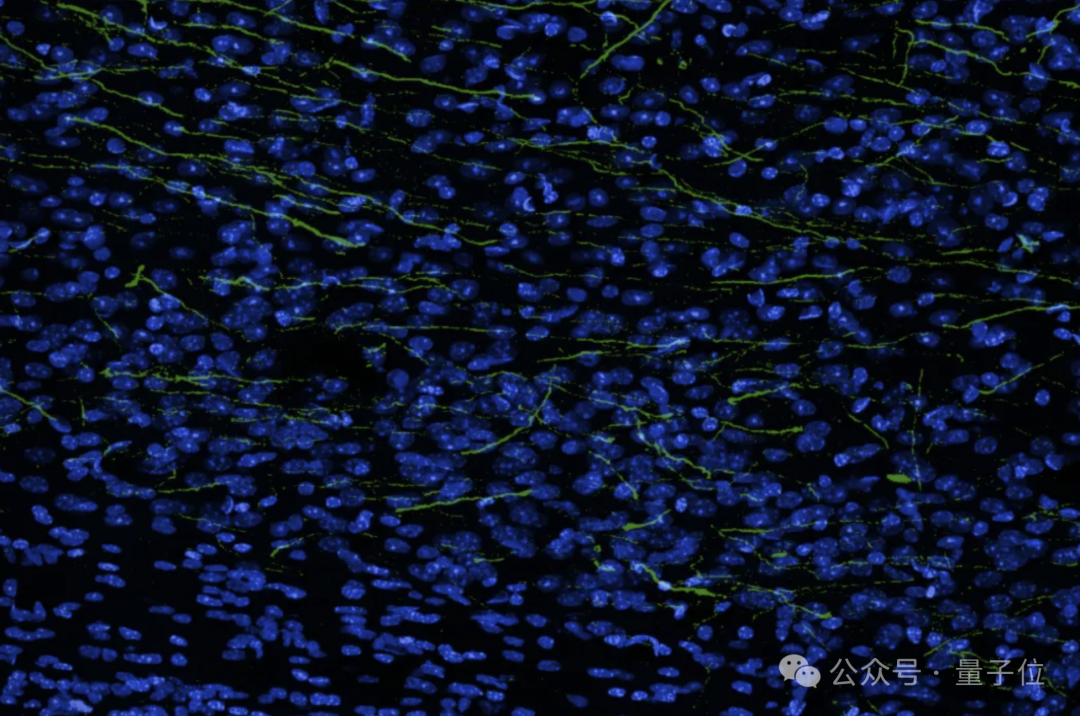

研究团队展示了一张大脑的横截面图像(蓝色表示细胞核),并表示人脑中看似空旷的空间实际上充满了轴突、树突和支持细胞,形成了密集的突触网络。

如图所示,绿色突出显示的细胞是实际的神经元轴突和树突,它们从生物混合移植物中延伸出来,在整个大脑中形成能够传输信息的连接。